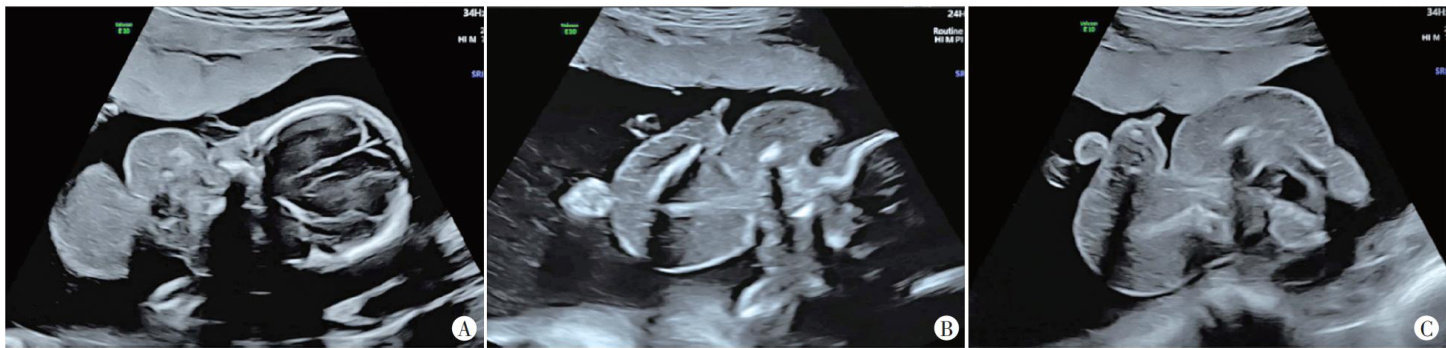

摘要 目的 探讨三维斑点追踪技术(3D-STI)评估主动脉瓣重度狭窄(AS)患者经导管主动脉瓣置换术(TAVR)后左心功能的临床价值。方法选取我院行TAVR的AS患者31例(AS组)和同期健康体检者31例(对照组),应用二维超声心动图获取左室舒张末内径(LVEDD)、收缩末内径(LVESD)、左室质量指数(LVMI),3D-STI获取左室整体主应变(GPS)整体纵向应变(GLS)整体圆周应变(GCS)整体径向应变(GRS)、三维射血分数(3D-LVEF),比较对照组与AS组,以及AS组术前与术后1、3、6个月上述参数的差异。结果与对照组比较,AS组术前LVEDD、LVESD、LVMI均升高,3D-LVEF、GPS、GLS、GCS、GRS均降低,差异均有统计学意义(均 P<0.001 ;AS组术后6个月LVMI仍升高,GPS、GLS、GCS仍降低,差异均有统计学意义(均 P<0.001 )。AS组术前、术后不同时间LVEDD、LVESD、LVMI、3D-LVEF、GPS、GLS、GRS、GCS比较差异均有统计学意义(均 P<0.05 )。与术前比较,AS组术后1个月LVEDD、LVMI均降低,GPS、GLS、GRS均升高,术后3个月和术后6个月LVEDD、LVESD及LVMI均降低,3D-LVEF、GPS、GLS、GRS及GCS均升高,差异均有统计学意义(均 P<0.001. );与术后1个月比较,术后3个月LVESDLVMI均降低,3D-LVEF、GPS、GLS、GCS均升高,术后6个月除LVEDD差异无统计学意义外,其余参数比较差异均有统计学意义(均 P<0.001 );与术后3个月比较,术后6个月LVMI进一步降低,GPS、GLS、GRS、GCS均进一步升高,差异均有统计学意义(均 P<0.001 )。结论AS患者TAVR后左心功能呈阶段性改善,3D-STI能早期、准确地评估其变化,具有一定的临床价值。